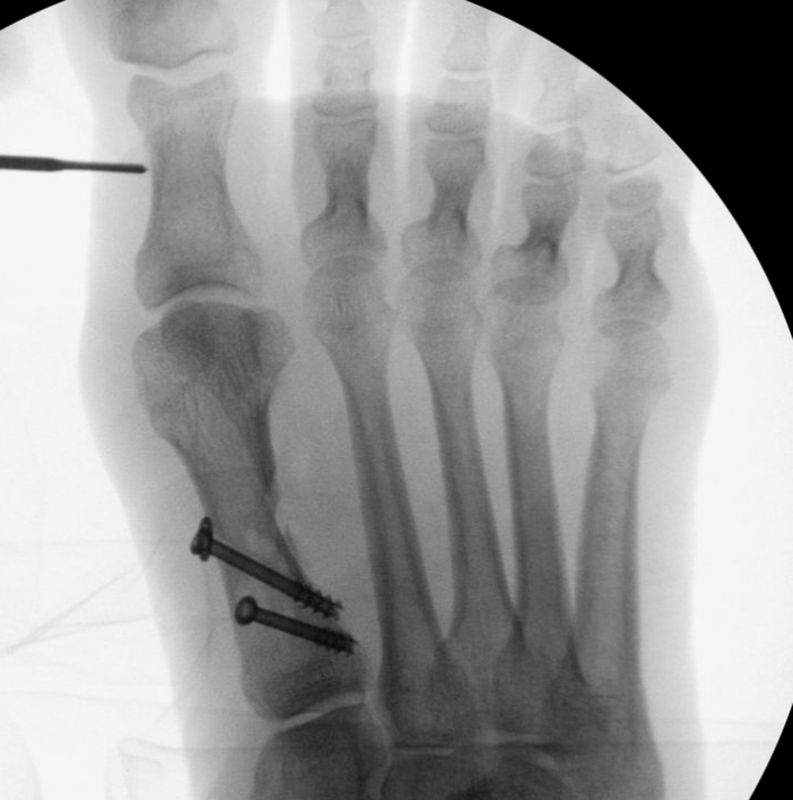

Ein häufig angewandtes Verfahren zur Korrektur eines erhöhten intermetatarsalen Winkels ist die laterale basale Closing Wedge Osteotomie des Os metatarsale I, entweder als Einzelverfahren oder in Kombination mit einer Isham-Osteotomie (sogenannte Doppelostetomie des 1. Mittelfußknochens) 2.

Die minimalinvasive Basisosteotomie des 1. Strahles stellt – entsprechend offenen Verfahren - die Operationstechnik mit dem größten Korrekturpotential dar. Sie kann entweder mit einer medialen Exostosenabtragung des Metatarsale-I-Köpfchens oder aber mit einer zusätzlichen minimalinvasiven subcapitalen medialen Closing wedge Osteotomie (Isham) kombiniert werden 2.  Diese Doppelosteotomie stellt ein hochpotentes Werkzeug zur Korrektur von schweren Hallux Valgus Fehlstellung dar. Im Unterschied zu offenen Verfahren an der Basis des Os metatarsale I sind minimal invasiv immer nur in Closing Wedge Technik möglich, womit eine leichte Verkürzung des 1. Strahls verbunden ist. Die Indikation entspricht dem offenen Techniken.

• Gute Stabilität durch Stabilisierung mit einer oder zwei perkutanen Schrauben möglich.

• Kanülierte Schrauben bis 50 mm Länge, 4 mm Durchmesser, Beilagscheiben.